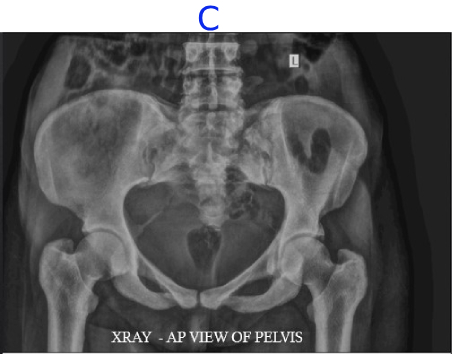

C) LEGENDS

• Diffusely increased density of the bones.

• Calcification of the right sacrospinous ligament.